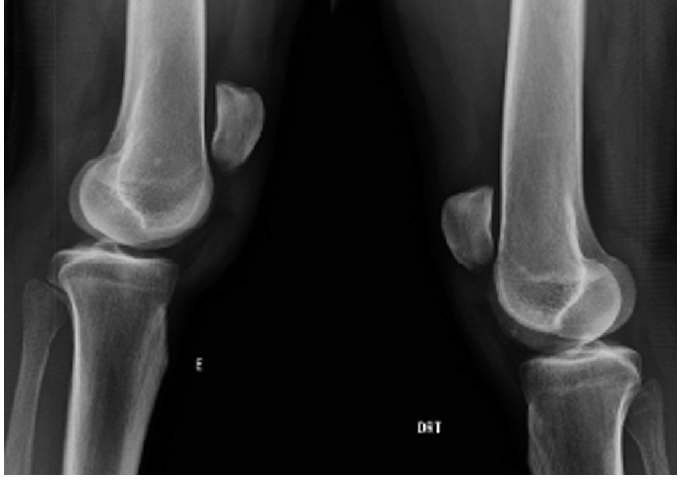

>>100936849She has patella alta, which basically means her kneecap is higher than it should be. Some random google images for example but the leg on the right is normal here, while the one on on the left has patella alta. It doesn't look like much but it means her balance is pretty fucked so she trips, stumbles, falls over, etc much easier than most people and can

as happened recently outright dislocate her knee if she's not careful.